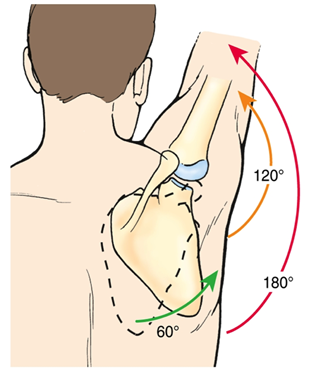

일반적으로 팔을 벌리는(팔벌려 뛰기 동작) 외전과 다르게 견갑골 관절면(Scapular plane)을 따라서 팔을 들어올리는 것을 스캡션(Scaption) 이라고 하는데요.

스캡션(Scaption)시에는 해부적구조상 극상근의 결의 방향과 힘의 방향이 그대로 일치합니다. 따라서 초음파로 동적 검사(Dynamic test) 시 극상근의 파열을 더 잘보려고 할 때 스캡션(Scaption)을 하라고 하면서 저항을 주면서(Full can test와 동일) 극상근의 파열부가 벌어지는것을 초음파로 확인해줄 때 사용합니다.

견갑골의 움직임은 3가지 움직임(Motion)과 2가지 미끄러짐(translations)으로 나눌 수 있습니다.

움직임(motion) - 한 축을 중심으로

ㆍ회전외회전(ER) / 내회전(IR)

ㆍ앞쪽 기울어짐(Anterior tilting) / 뒤쪽 기울어짐(Posterior tilting)

ㆍ상방회전(Upward rotation) / 하방회전(Downward rotation)

견갑골은 효율적인 팔 움직임에 꼭 필요하며, 특히 견갑골과 상완골 사이의 조화로운 움직임을 비율을 "견갑상완리듬"이라고 따로 말하고 있습니다.